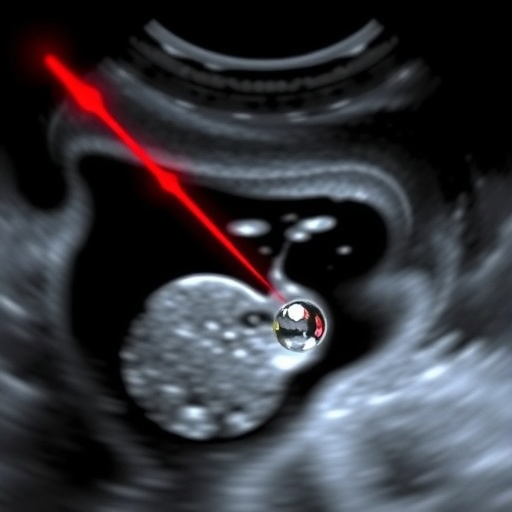

Central to this technology are nanodroplets—tiny, engineered particles designed to respond to specific light frequencies. Unlike conventional ultrasound contrast agents, these nanodroplets remain inert under regular imaging, only transitioning to highly echogenic microbubbles upon laser stimulation. When exposed to finely tuned laser pulses, the nanodroplets rapidly vaporize, expanding into microbubbles that scatter ultrasound waves with much greater intensity. This transformation dramatically amplifies the ultrasonic signal, thereby allowing for precise localization of these agents in the body.

What makes this technique revolutionary is its ability to provide spatial resolution beyond what was previously achievable by ultrasound alone. By synchronizing laser activation and ultrasound detection, the researchers were able to capture the exact moments when nanodroplets convert to microbubbles, effectively creating a map of targeted structures with micrometer-scale precision. The heightened contrast and resolution make it possible to visualize minute biological features, including cellular-level vessel structures and microenvironmental changes, which were previously undetectable using standard ultrasound methods.